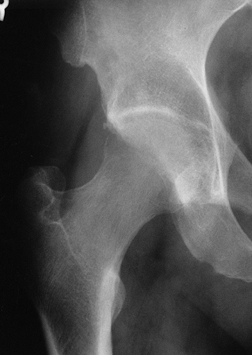

involved, it may be pathognomonic (Fig. 125.7).

presence of large amounts of edema fluid (Fig. 125.8 and Fig. 125.9).

In osteonecrosis, the changes are usually limited to the superior

the double-line sign on T2-weighted images is essentially pathognomonic

for osteonecrosis (Fig. 125.7).

![]() |

|

Figure 125.7. MRI images of a patient with bilateral osteonecrosis seen on plain radiographs. The T1-weighted image (top panel) shows subchondral lesions bilaterally composed of alternating areas of low and high signal intensity. The T2-weighted image (bottom panel) shows a high signal line inside the low signal on the right (double line sign). On the left,

the lesion in the proximal portion of the femoral head has diffuse low signal intensity whereas the area below the necrotic lesion (asterisks) is isointense, indicating coexisting edema. (Courtesy of Dr. S. Hoffman, Danube Hospital of Vienna, Austria. From Bauer T, Plenk H. The Pathology of Early Osteonecrosis. Semin Arthroplasty 1998;3:192, with permission.) |